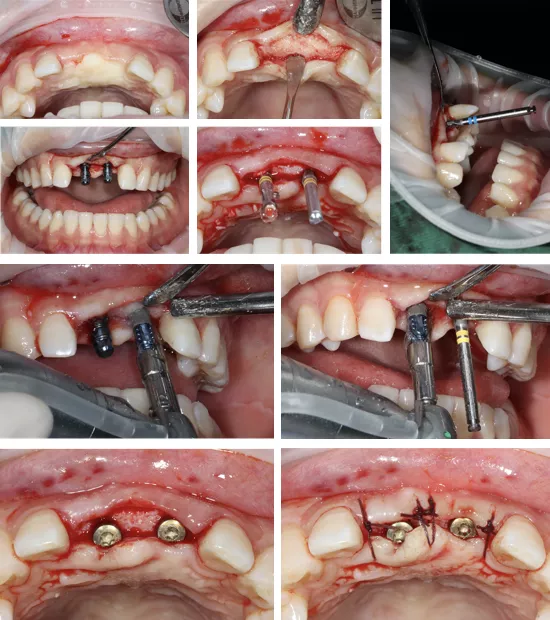

·      口内外消毒铺巾后,常规局麻下翻瓣,拔除患牙#11#21残根。

·      唇腭侧翻瓣显露牙槽骨壁。清整骨面后腭侧开窗,去除阻生埋伏多生牙。

·      采集自体血混合bio-oss骨粉0.75g植骨盖膜。

制作粘接固位临时修复体,基底部悬空。

种植一期手术

·      计划术区沿牙槽嵴顶做直线切口,翻瓣计划植入Straumann BLT 3.3*12mm各一枚。分别上3.6*5愈合基台。